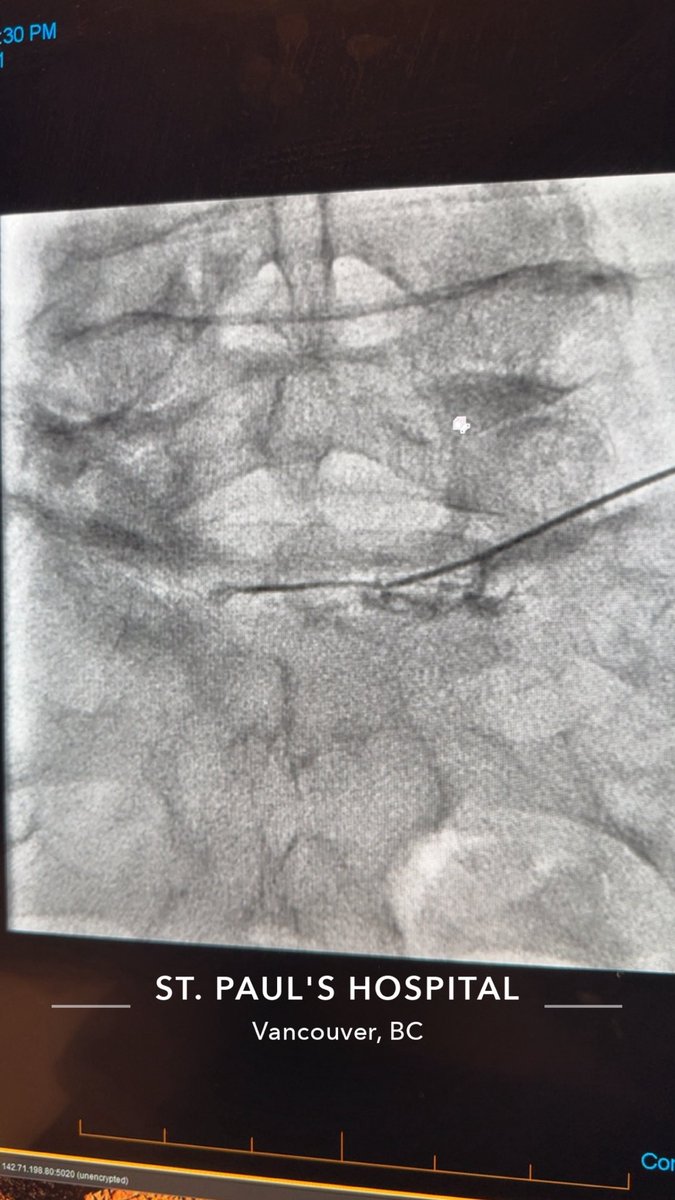

@Eyaaaad Ripcord suture

يلاحظ اجراء المريض لعملية انبوب للماء الازرق (لارتفاع ضغط العين)

وفيه حال كان الانبوب بدون صمام يتم وضع خيط داخل الانبوب وتركه في ملتحمة العين وذلك لازالته بعد اشهر

الخيط بعمل كـ flow resistance يبقي ضغط العين بالحد المعقول حتى لا يكون الضغط بعد العملية مباشرة صفر